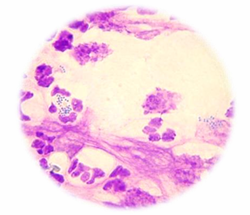

What is being shown in this cytology?

Superficial pyoderma (Left)

Deep pyoderma (Right)